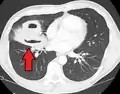

A subpleural abscess.

Pulmonary abscess on CT scan